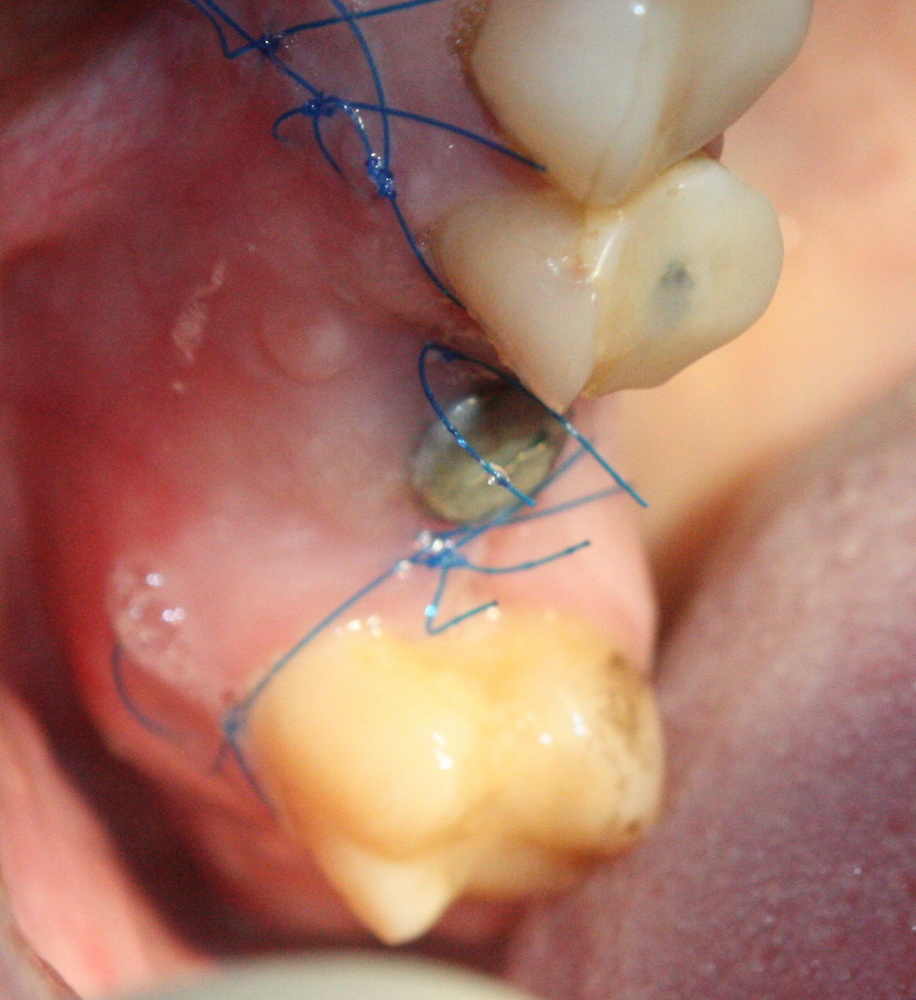

Немедленная имплантация — оптимальное решение в любой клинической ситуации